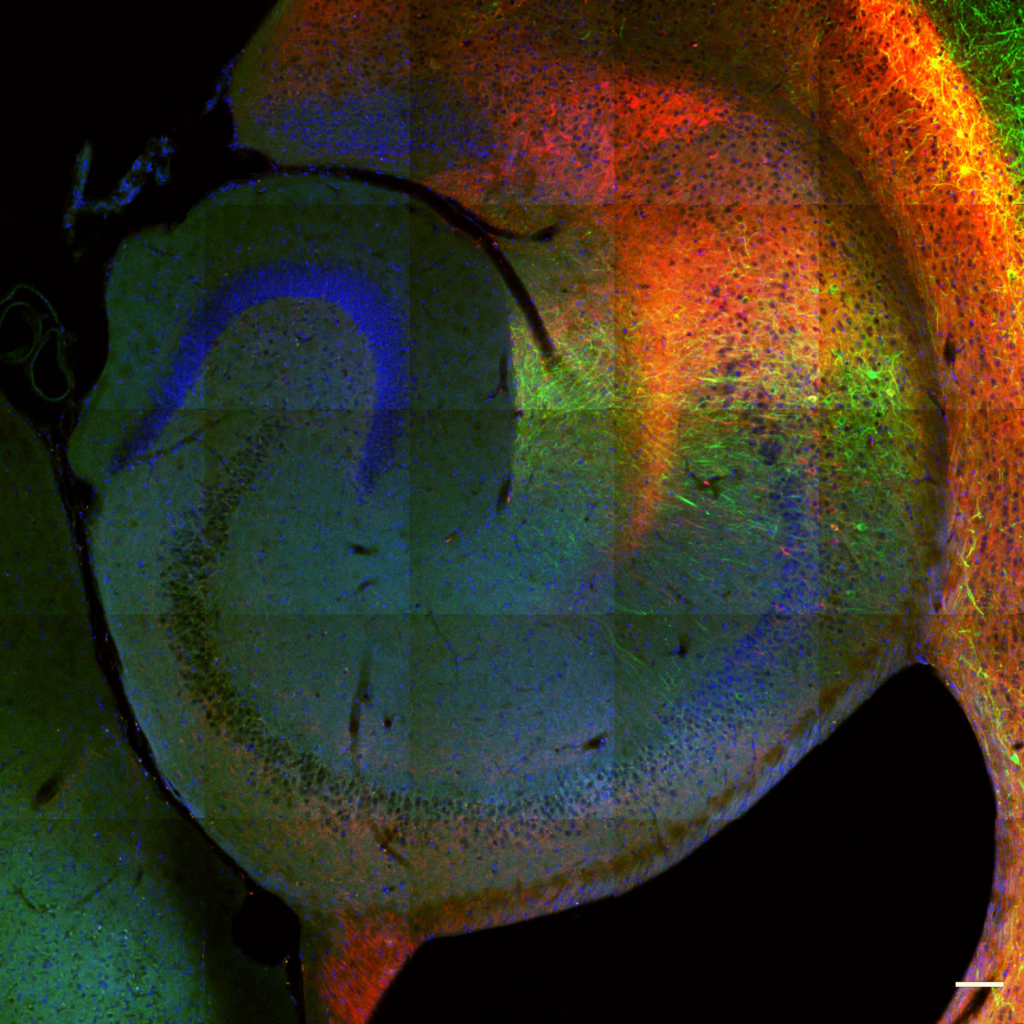

Nearly 60 million people in the United States are living with a mental illness, yet the available treatments remain inadequate. In the Donegan Lab, our goal is to understand how neural circuits are altered in psychiatric disease so that we can find new and more effective therapeutic strategies. Toward this end, we use rodent models to examine molecules, neural circuits, and ultimately behavior, to determine how various risk factors can lead to mental illness.

Curiosity We believe that seeking out new knowledge and challenging previously held beliefs drives discovery. We aim to understand the neurobiological mechanisms that underlie complex behaviors associated with psychiatric disease.

Innovation We believe that innovation is required to move science forward. In our lab, we use novel techniques and develop new ideas to change our understanding and approach to mental illness.